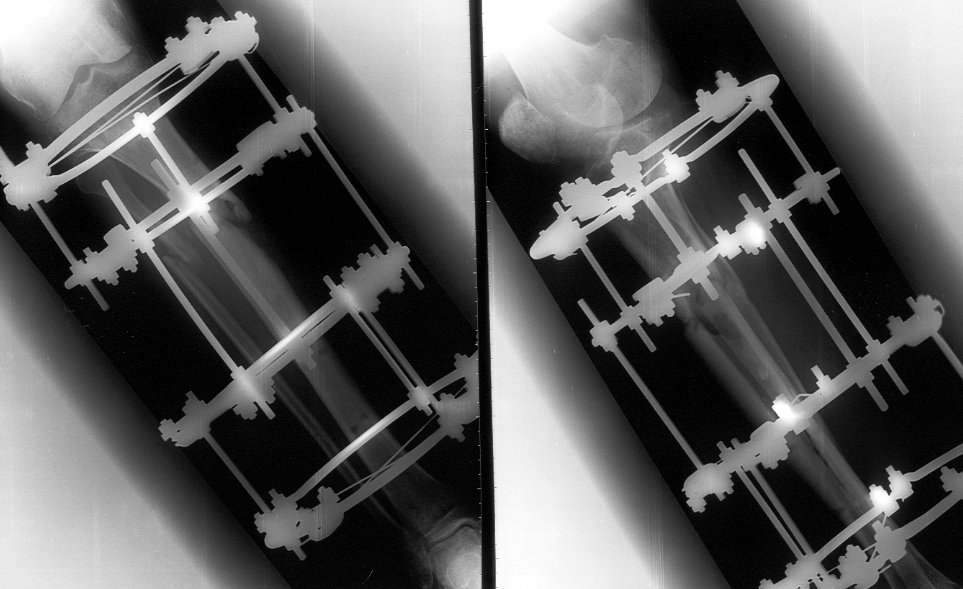

45 y/o male sustained in MVA 3 months ago. Had closed proximal third left tibial fracture. Initially treated in rural hospital where IM nailing was attempted but complicated with longitudinal tivial split down to tibial shaft to distal tibial metaphysis. Nailing was abandoned and cast was applied and patient was reffered to us.

We applied Ilizarov frame, which was performing nice until 1 month ago when patient started to bear full weight. Yesterday patient presented to us. Gross Ilizarov frame instability and fracture movement was detected. Patient has minor pain in FWB, pins are infection free.

![]() |